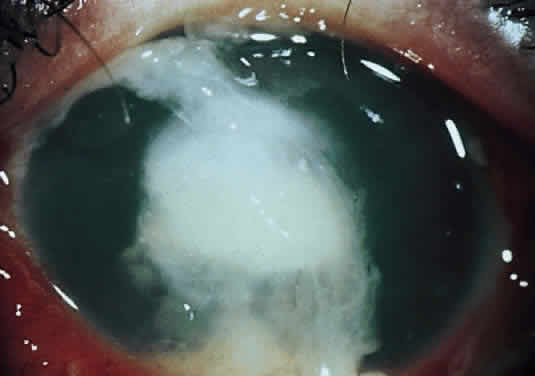

Clinically, the infected staphylococcal corneal ulcer presents with a yellow-white, well-demarcated area of infiltrate, which appears directly beneath an epithelial defect (Fig. 2). On occasion, multiple, small satellite lesions may develop. The infection may initially be superficial; however, if inadequately treated it can produce a mid to deep stromal abscess that may eventually lead to perforation. Stromal edema and white blood cell migration frequently surround the dense infiltrate and clear as the infection comes under control. Although there may be a marked anterior chamber reaction with hypopyon, the ulcer more frequently is indolent, with only a minimal inflammatory reaction.34